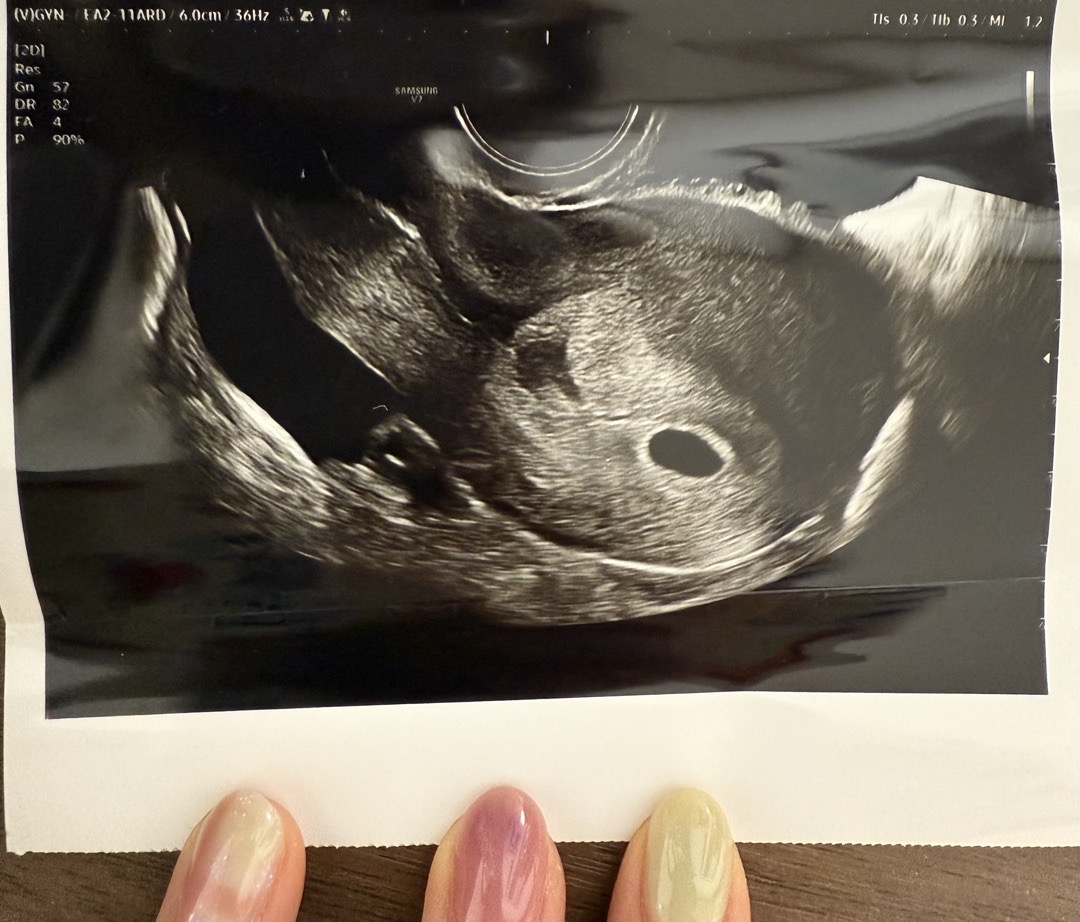

5주 1일차 아기집 보고 왔어요!

결혼한지 한 달 됐는데 아기가 찾아왔어요 정말 서프라이즈로 찾아 온 아기라 너무 신기하고 아직은 실감이 안나요ㅎㅎ 막생은 8/13 이고 이번 달 예정일이 15일이라 당연히 하겠거니하고 저번주 토요일엔 술까지 마셨는데.. 원래 주기가 일정한데 이틀이나 미뤄지고 감기몸살이 오길래 아 설마? 하고 어제 테스트기했더니 두 줄이 떠서 바로 병원 달려갔어요. 아기집 잘 보고 예정일 5/20로 받고 왔습니당☺️ 5주차 0일 아기집 크기가 0.94인데 괜찮은건가요?? 병원 다녀오니 뭔가 아랫배가 살짝 쿡쿡 쑤시고 골반도 아프구 피곤하고.. 임신증상이 훅 다가오는 것 같아요 ㅎㅎ 다들 임신기간 힘내시고 모두 건강한 아기 출산해요! ㅎㅎ